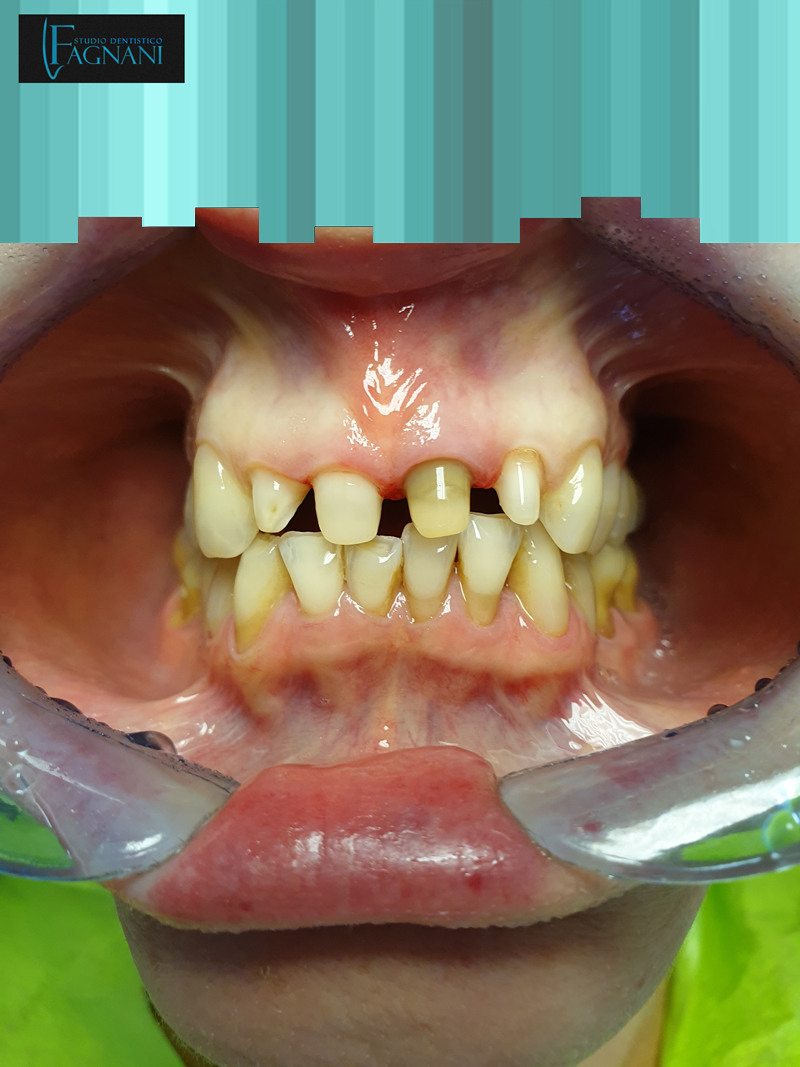

Caso 5

Grave caso di parodontite risolto con l’estrazione dei denti dell’arcata superiore e chirurgia guidata per tecnica all on four.

Prima: